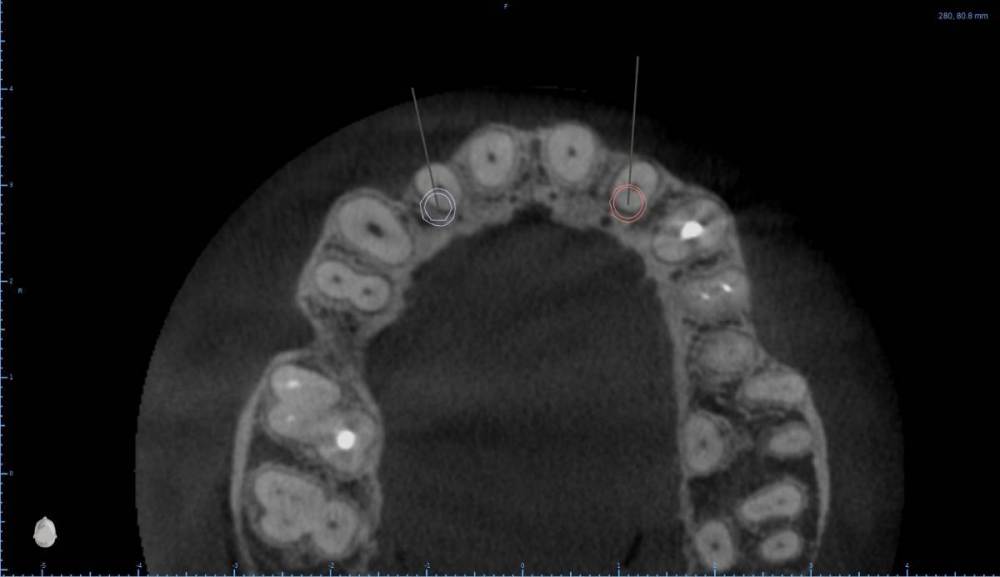

Женька Опубликовано 6 августа, 2022 Поделиться Опубликовано 6 августа, 2022 В общем планируется большая (по крайней мере для меня) работа. Вот такой товарищ у нас. Делали бы НКР в области 2.5з? или поставили бы чисто по кости, а оголённый участок закрыли присыпкой и мембраной? Также вопросы по двойкам имеются. Бугор есть, сразу оговорюсь, правда только с одной стороны. Также не понятно пока "как его правильно готовить" этот бугор, чтобы закрыть такие дефекты вестибулярной пластинки. Скрины постарался нарезать по максимуму. Там ещё будет ортодонтия конечно же. Интрузии, движения всякие и тд) Да, знаю, что планировать без цифрового гипса неправильно, но что имею. Ссылка на комментарий

Irouil Опубликовано 6 августа, 2022 Поделиться Опубликовано 6 августа, 2022 Если будет ортодонтия, то не проще ли вытянуть двойки чтобы вырастить ткани? ИДР тут нужен основательный очень, винты придётся крутить тоже очень длинные В области премоляра не вижу смысла что-то графтить, если хочется чего-то натолкать - можно стружки со сверла упаковать в дефект, но имхо не обязательно. А если сместить винт небно и чуть аннулировать, преп только пилотным и дальше конденсировать... ну Вы поняли 1 Ссылка на комментарий

Женька Опубликовано 6 августа, 2022 Автор Поделиться Опубликовано 6 августа, 2022 (изменено) @Irouil ортопед вряд ли согласится на такое. Может тогда проще пойти отсроченно? Удалить, кюретаж, губку в лунки и мэриленд (каппа с зубами) на 3 месяца. А потом уже выдумывать пластики по факту новой КТ? Винты 14мм максимум что есть По премоляру вот тоже думаю, что игра не стоит свеч. А двойки... признаться я уже ортопеду сказал, что отсрочено пойдём... хотя конечно пока всё ещё раздумываю Изменено 6 августа, 2022 пользователем Женька Ссылка на комментарий